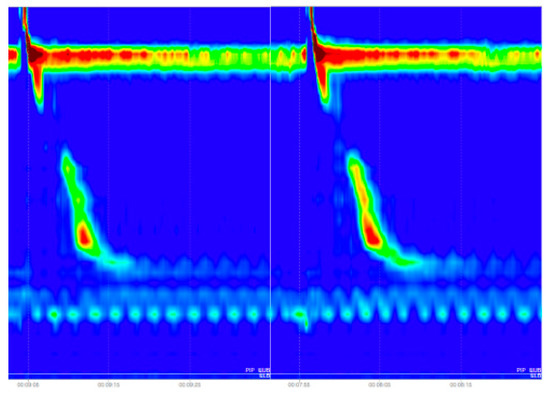

As we can see in Figure 7, in the case of Ineffective Esophageal Motility and Fragmented Peristalsis patterns the evaluation metrics were lower than in the case of other disorders, which can be explained by the nature of these images. In case of the Fragmented Peristalsis we looked at the Fragmented Contractions swallowing pattern class and in the case of Ineffective Esophageal Motility we took into consideration the Week swallowing pattern class, but these two swallowing patterns were very similar (see Figure 8), leading the trained model to make some mistakes when trying to classify them (the inter-class similarity was very high, again explaining some of the mistakes recorded).

Figure 8.

The left image depicts a week swallow, while the right image shows a fragmented contraction.

The final results were affected by the inter-class similarity problem, which in some swallowing disorder classes was very high, which resulted in a lower evaluation score for some of the esophageal motility disorder classes. In the case of Ineffective Esophageal Motility and Fragmented Peristalsis patterns, the evaluation metrics were lower than in the case of other disorders, which can be explained by the nature of these images. In case of the Fragmented Peristalsis we looked at the Fragmented Contractions swallowing pattern class and in the case of Ineffective Esophageal Motility we took into consideration the Week swallowing pattern class, but these two swallowing patterns were very similar, leading the trained model to make some mistakes when trying to classify them (the inter-class similarity was very high, again explaining some of the mistakes recorded).